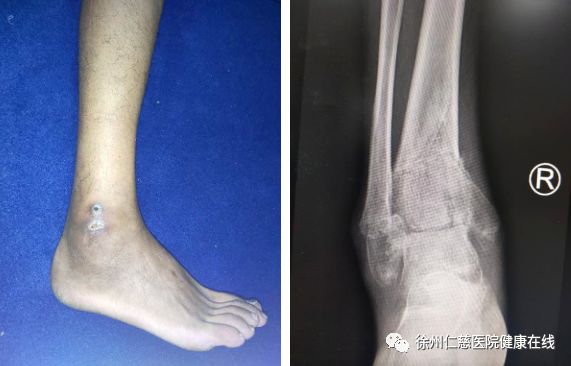

35岁的胡师傅,从梯子上摔下导致踝关节骨折,听信“民间偏方”,使用草药进行外敷治疗,结果两个月后,右脚疼痛、肿胀依旧,还生了水泡,病情愈发严重,胡师傅非常后悔,来到必威官方首页官网betway足踝科治疗,医生检查后,告诉他“已经错过了最佳手术时机”。

胡师傅家住徐州睢宁,2个月前,胡师傅在家中刷墙时不小心从梯子上摔下,感觉右踝关节肿胀、畸形,后去当地医院拍片显示“右踝关节骨折”,医生建议他住院手术,但胡师傅不想手术,胡师傅的母亲听来一个民间偏方,用几种草药混合成膏药给胡师傅抹上,据说“治疗骨折效果很好”。于是在家养了40天,右脚还是疼痛、肿胀,不能下地,内外踝还有水泡形成,胡师傅再到医院复查,医生说很可能是他抹上的不明膏药导致的,建议他去专业的足踝科仔细检查。

胡师傅来到betway在线登陆足踝外科,二病区徐明亮主任给他做了详细检查。踝关节骨折,没有复位固定,已经导致骨折畸形愈合,错过了手术最佳时机,后期可能导致创伤性关节炎。医生原本计划进行截骨矫形,但因患者的内外踝伤口未完全愈合,只能等待皮肤完全愈合了再手术。